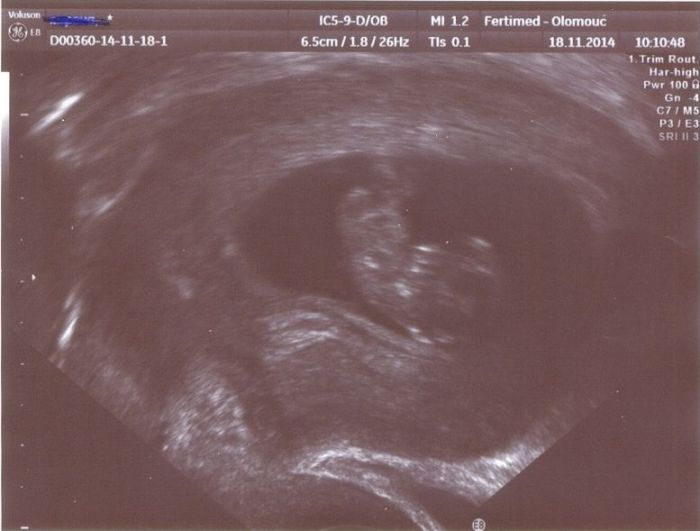

Díky za informaci. Mě zatím nic nebolí ani jsem neměla nevolnosti,tak jsem byla ráda.Pošlu foto když jsem byla v týdnu 9+3.Prcek se furt povaluje na zádech i minulý týden když jsem byla v poradně tak si ležel na zádech.